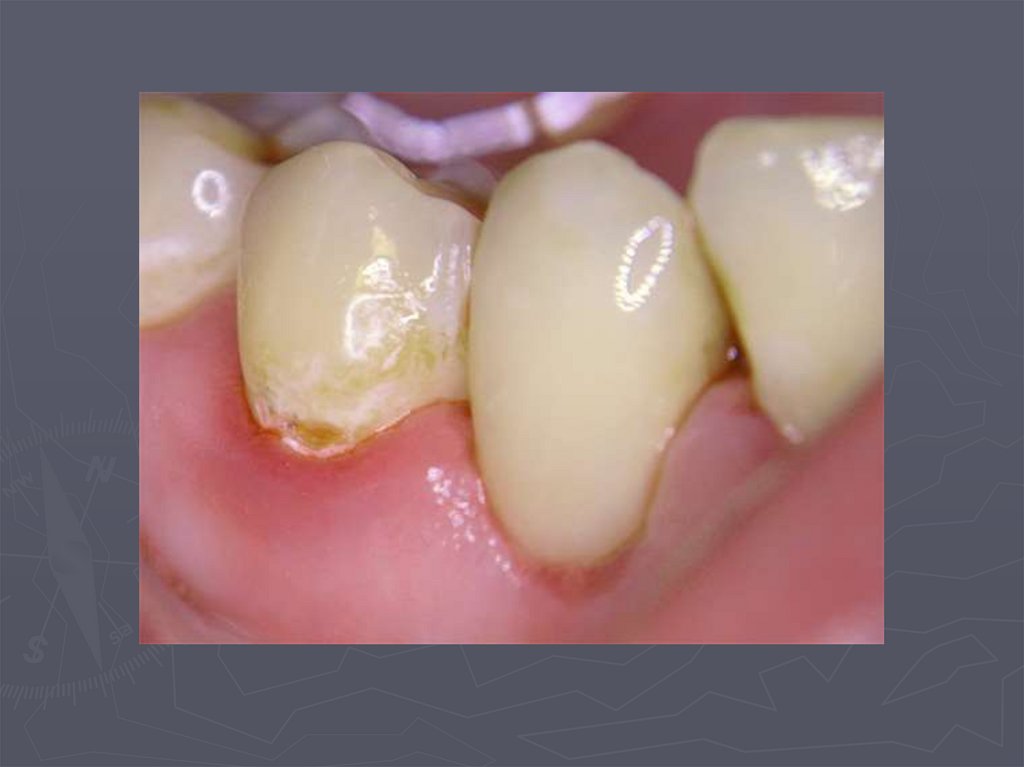

Циркулярный кариес

4. ОСОБЕННОСТИ КЛИНИЧЕСКОГО ПРОЯВЛЕНИЯ КАРИЕСА У ДЕТЕЙ РАННЕГО ВОЗРАСТА

У детей в возрасте от 1года до 3 лет КАРИЕС

чаще возникает:

► на зубах, имеющих порочно развитые ткани в виде

гипоплазии;

► ткани этих зубов недостаточно минерализованы;

► чаще поражаются резцы;

► затем моляры и клыки;

► преимущественная локализация кариозной полости на

вестибулярной и контактной поверхности резцов ;

► а также в фиссурах моляров;

► нередко кариес начинается в пришеечной области;

► процесс распространяется вокруг всей коронки;

► формируется циркулярный кариес.

5. ОСОБЕННОСТИ КЛИНИЧЕСКОГО ПРОЯВЛЕНИЯ КАРИЕСА ВРЕМЕННЫХ ЗУБОВ У ДЕТЕЙ РАЗЛИЧНОГО ВОЗРАСТА

При клиническом осмотре выявляются:

► кариозные полости по глубине мелкие;

► имеют плоскую форму;

► входное отверстие в кариозную полость широкое

► эмаль по краям кариозной полости хрупкая;

► инфицированный дентин в полости влажный.

,

8. Циркулярный кариес